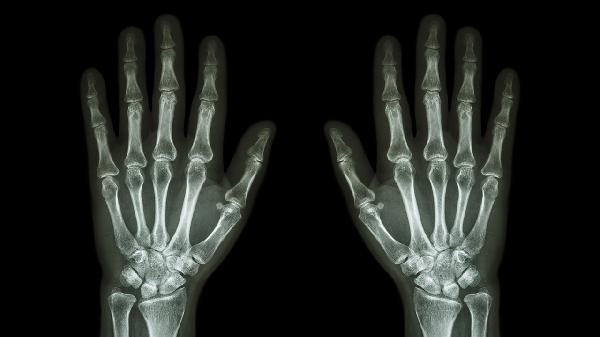

约30%银屑病患者伴随关节病变,特征为指甲凹陷和腊肠指。皮肤损害常先于关节症状出现,X线可见笔帽样骨侵蚀。治疗需联合阿维A胶囊、柳氮磺吡啶肠溶片等药物,生物制剂如司库奇尤单抗注射液对皮损和关节炎均有效。